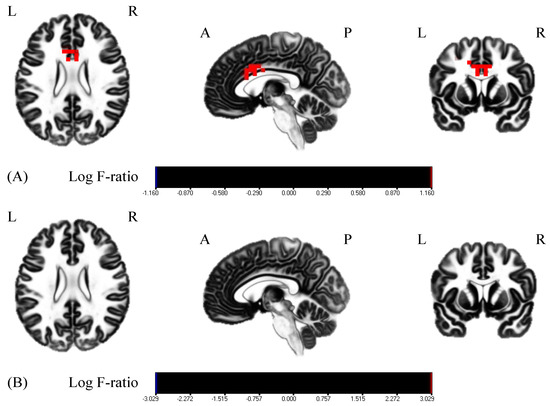

| Group | Brain Region | BA | MNI Coordinates | p-Value |

|---|---|---|---|---|

| (x, y, z) | ||||

| MI + rPMS | Anterior cingulate cortex | 24 | (−5, 10, 30) | p < 0.05 |

| 32 | (−15, 15, 35) | |||

| 33 | (−5, 10, 25) |